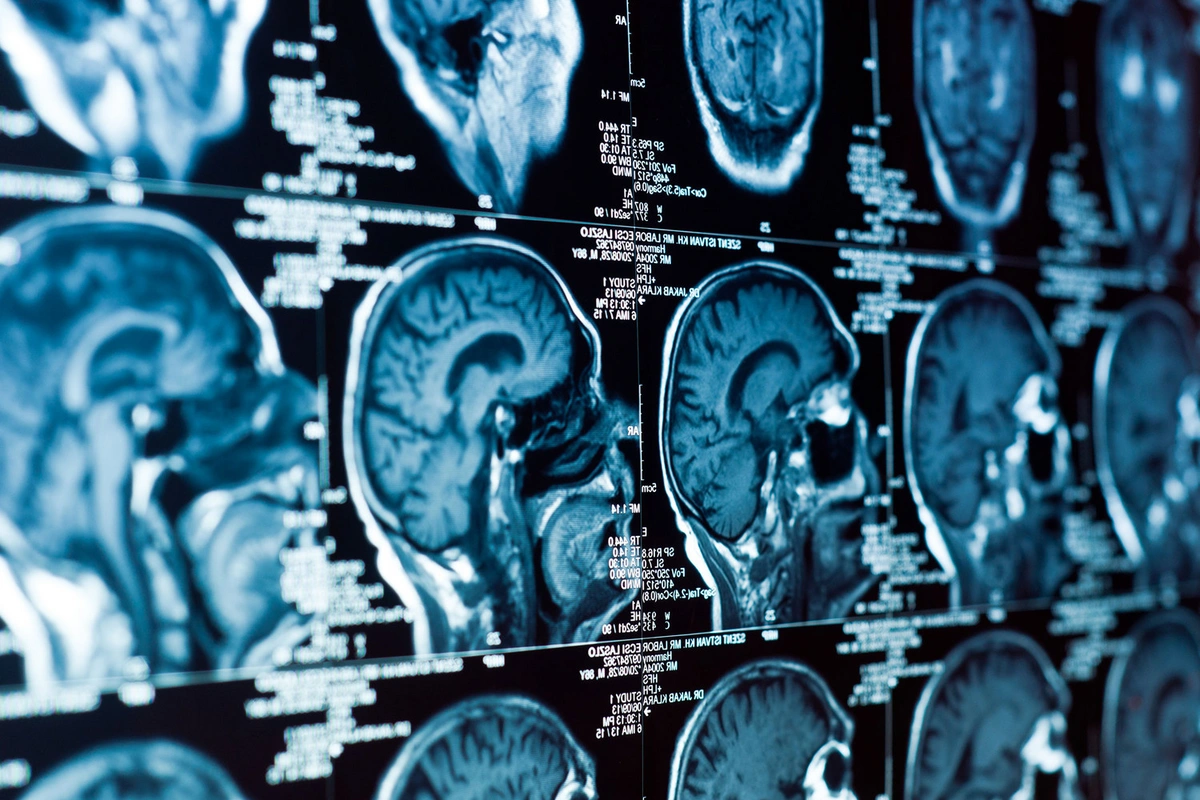

Ученые из Университета Тасмании установили, что люди с низким социально-экономическим статусом на 33% чаще переносят инсульт по сравнению с более обеспеченными слоями населения.

Авторы проанализировали медицинские данные жителей Тасмании - включая госпитализации и летальные исходы - за период с 2007 по 2020 год. Анализ показал, что социальное положение напрямую связано с риском развития заболеваний сосудов. В частности, выяснилось, что люди с низким социально-экономическим статусом на 33% чаще страдают от инсультов.